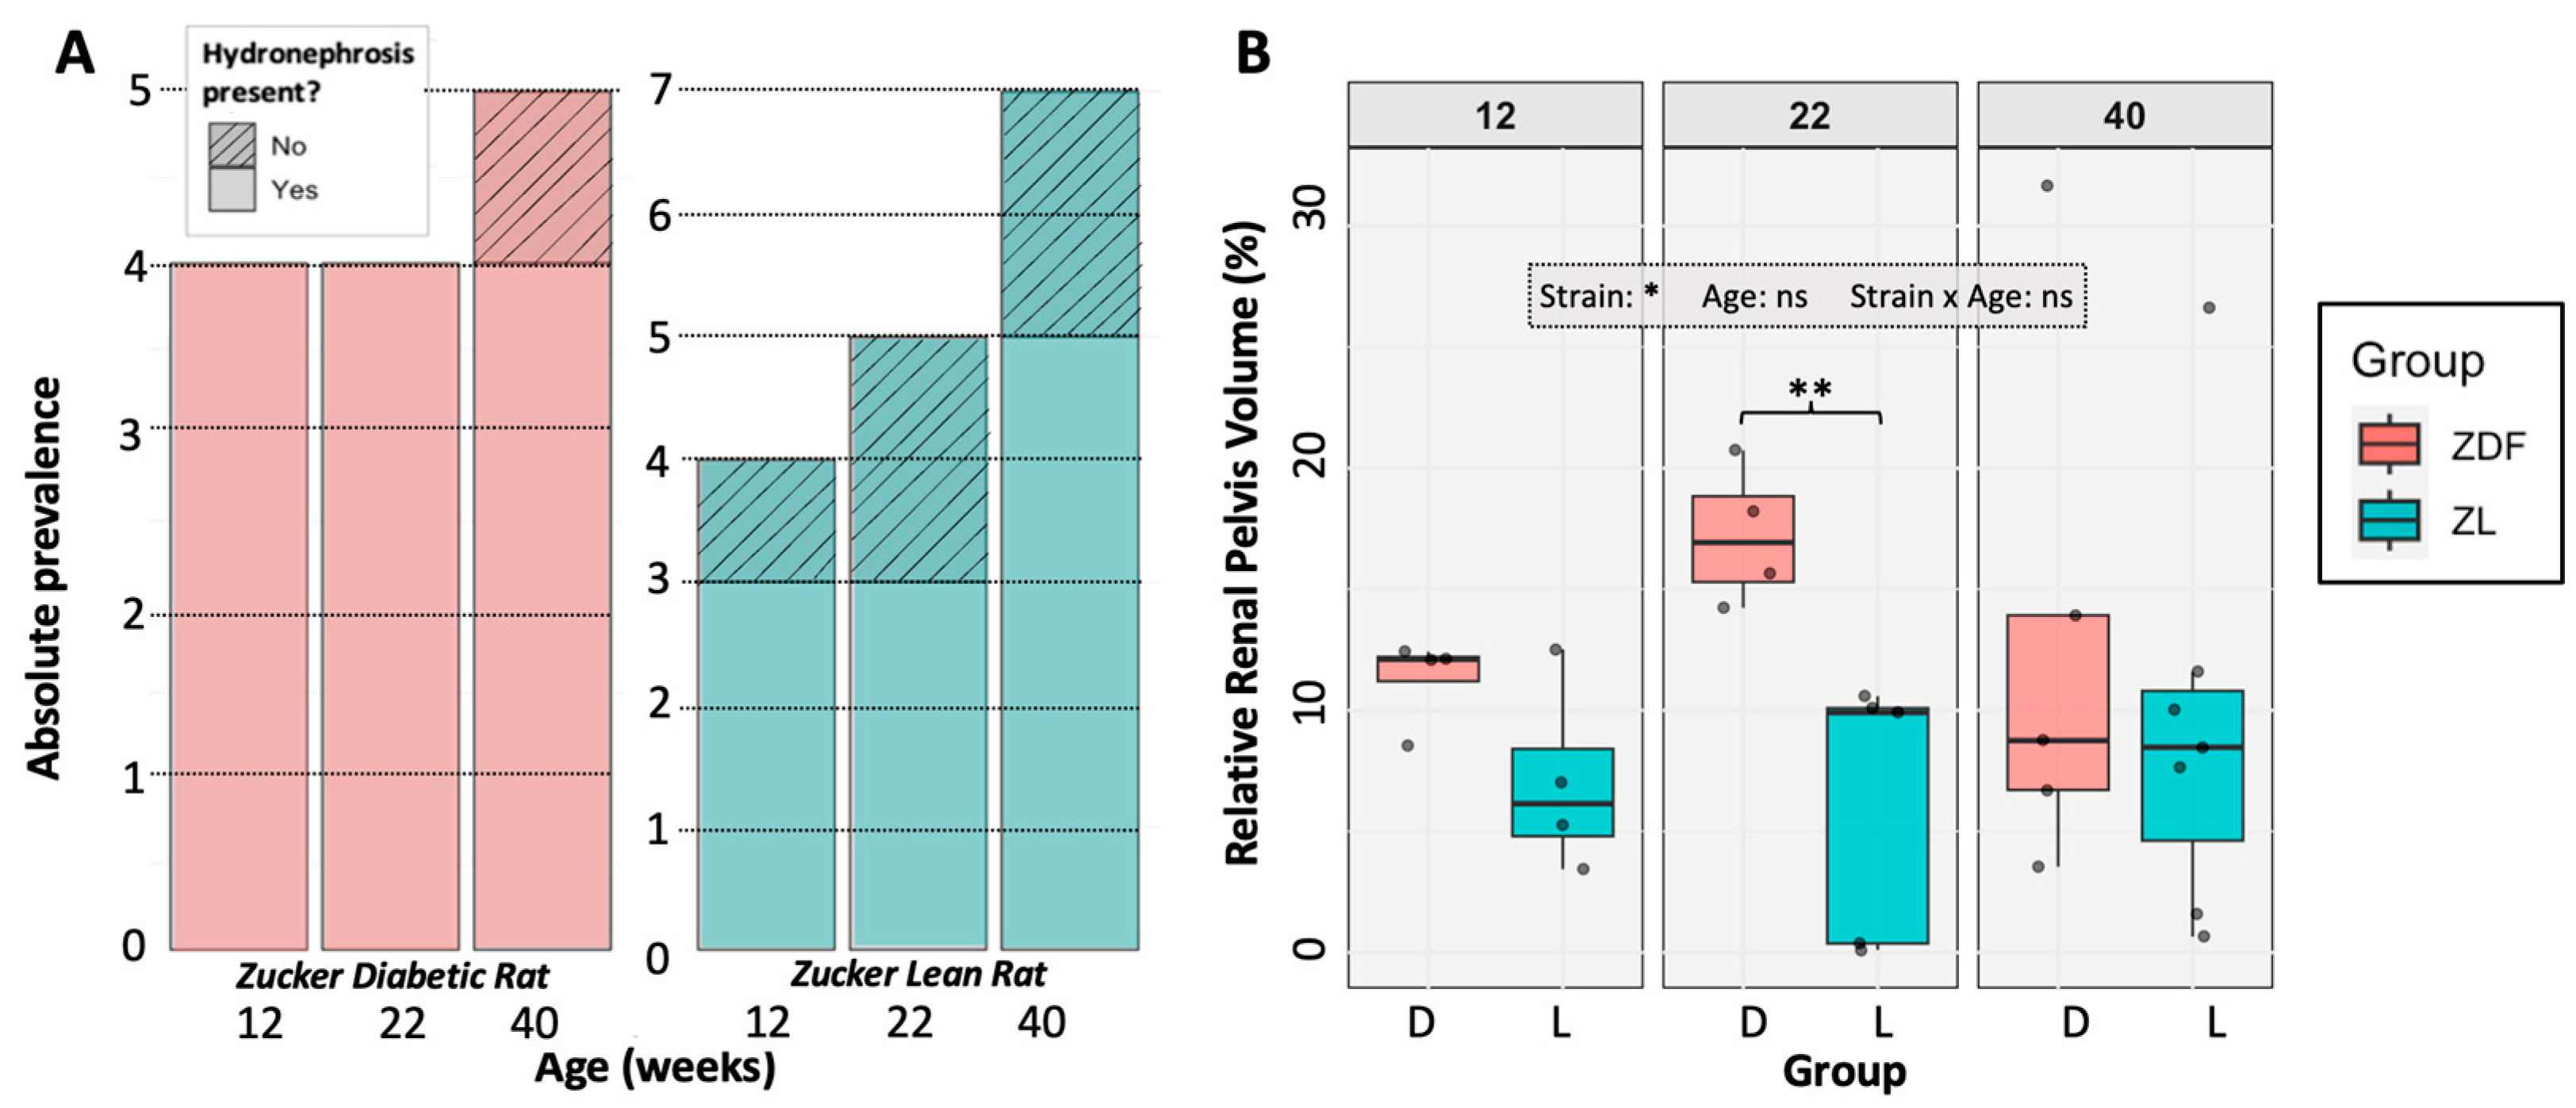

3.3. Hydronephrosis Prevalence and Severity

3.4. The Impact of Hydronephrosis on Renal Function and Anatomy

4.1. The Effects of Hydronephrosis on Healthy (ZL) Rats